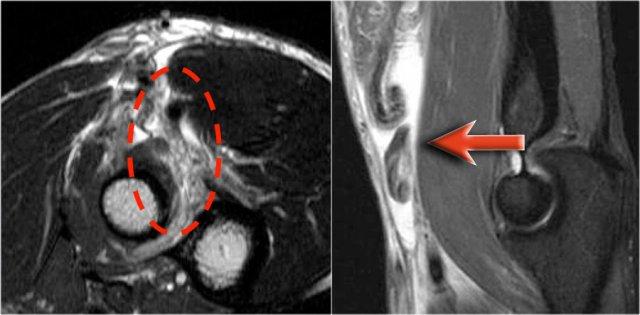

Arthrosis in valgus overload syndrome

Do quá tải valgus, có các lực cắt tác động lên phần sau-trong của khớp cánh tay-trụ.

Lưu ý tình trạng xơ cứng dưới sụn được thấy trên ảnh T1W (mũi tên đỏ).

Trên hình ảnh T2W có phù tủy xương dưới sụn và mất sụn khớp (mũi tên vàng).

Đây là hình ảnh của một vận động viên bóng chày 20 tuổi.

Trên các hình ảnh mặt phẳng coronal, bó trước của dây chằng UCL hiện rõ đẹp, nhưng lưu ý rằng có sự hình thành gai xương ở phần trong của khớp (mũi tên đỏ).

Khi chúng ta đi xa hơn về phía sau có một vùng nhỏ có tín hiệu thấp (mũi tên vàng), đây là một chỗ bong gân của một phần dây chằng bên trụ (UCL).

Điều này được thể hiện rõ hơn trên phim X-quang.

Khi quan sát trên lát cắt ngang (axial), chúng ta có thể nhận thấy sự hình thành gai xương khổng lồ.

Lưu ý rằng dây thần kinh trụ (mũi tên màu xanh) nằm cạnh các gai xương này và những bệnh nhân này có thể biểu hiện bệnh lý thần kinh trụ.